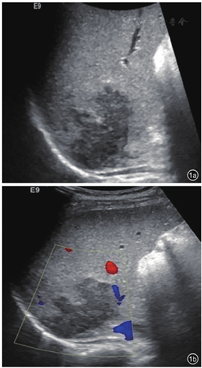

患者,女性,45岁,因糖尿病行体检无意间发现肝右叶肿物3 d入院。无腹痛、腹胀,无寒战、发热,无皮肤、巩膜黄染,无乏力,无体重减轻等。既往2型糖尿病病史,注射胰岛素治疗,血糖控制良好。无肝炎病史,无牧区居住史,无饮酒史,无肿瘤家族史。查体:体温36℃,肝、脾肋下未触及,腹平软,移动性浊音阴性。实验室检查:白细胞计数10.29×109/L,肝功能正常,乙型肝炎表面抗原和核心抗原阴性,甲胎蛋白(alpha fetoprotein,AFP)、糖类抗原19-9(carbohydrate antigen 19-9,CA19-9)及癌胚抗原(carcino-embryonic antigen,CEA)均阴性。腹部超声示:肝脏回声均匀,肝右叶被膜下探及低回声,约5.9 cm×3.6 cm,形态不规则,边界不清,周围无声晕,后方回声未见增强,内未见明显血流信号(图1)。超声诊断:肝右叶肿物,声像图不支持典型肝癌,血管源性病变待排。静脉团注2.4 ml声诺维造影剂,肝脏超声造影示:肝右叶上段可见一大小为5.3 cm×3.4 cm的弱回声团,形态不规则,超声造影呈动脉期高增强,门脉期及延迟期低增强,呈"快进快出"模式(图2)。超声造影诊断:肝右叶实性占位,倾向恶性,建议超声引导下穿刺活检明确性质。腹部CT示:肝右后叶肿物,边界不清,大小约4.1 cm×4.8 cm,分叶状,肿物密度欠均匀,平扫为低密度,增强扫描呈轻度延迟强化,病变侵犯门脉右支分支,致管腔狭窄,管壁水肿(图3),倾向炎性肉芽肿性病变,与肿瘤待鉴别,建议穿刺活检。腹部MRI示:肝右后叶肿物,范围约3.6 cm×4.8 cm,分叶状,边界不清楚,T1加权像(T1 weighted image,T1WI)低信号,T2加权压脂像(T2 weighted image/fat suppression,T2WI/FS)稍高信号影,弥散加权成像(diffusion weighted image,DWI)高信号,增强扫描轻中度延迟强化,病变侵犯门脉右支分支(图4)。腹部MRI诊断:肝右后叶肿物,考虑肝癌可能性大。临床初步诊断:肝右叶实性占位,肝癌待排。患者行超声引导下肝肿物穿刺,组织病理学回报:可见梭形细胞增生,伴炎细胞浸润,结合免疫组化,考虑炎性肌纤维母细胞性病变(图5)。免疫组化结果显示:AE1/AE3(-),Vimentin(3+),Actin(1+),SMA(2+),Desmin(-),s-100(-),CD1a(-),CD21(-),CD35(-),CD68(3+),Ki-67(10%)。患者定期复查,未行治疗。5个月后复查腹部MRI示:原肝右后叶肿物,现已显示不明确,仅局部可见小片状异常信号,T1WI低信号,T2WI/FS低信号,DWI无明显扩散受限,增强扫描强化程度低于周围肝实质(图6),符合良性病变,请结合临床及病理。结合既往穿刺活检及影像学随访病灶消退病史,患者最终诊断为肝脏炎性肌纤维母细胞瘤。随访至今21个月,患者一般情况良好,无复发。

HIMT的超声、超声造影及CT、MRI影像表现多样,可能与不同病灶中病理组织学成分的比例及分布的差异相关[8]。超声常表现为单发、低回声肿块,内回声不均,形态多不规则,在特定切面可呈葫芦状、花生状或多结节融合状等特征性形态,部分病灶周围呈宽带状高回声[9],常无晕环,病灶后方多无明显增强或衰减。由于HIMT中纤维组织增生与慢性炎细胞比例不同,病灶凝固性坏死成分存在差异,随着病程的变化,其声像图表现多样。莫国强等[9]随访7例HIMT病灶发现,3例原低回声病灶内出现高回声,2例原病灶周边低回声晕消失并在11个月后为高回声圈替代,考虑为病变后期或陈旧性病灶内纤维组织增生、形成假包膜所致。本例患者肝脏肿瘤形态不规则,边界不清,与既往报道一致,结合穿刺病理,考虑肿瘤为病变后期,以增生为主。彩色多普勒血流显像(color Doppler flow imaging,CDFI)示肿块内多无明显血流信号,少数内部及周围可探及血流,血流阻力指数(resistance index,RI)多小于0.5[7]。由于不同病灶内新生血管血供程度不同,病灶内纤维化及炎性细胞成分有差异,HIMT超声造影模式亦可呈多样性,但文献报道[10,11],多数HIMT超声造影表现为恶性肿瘤增强模式,即"快进快出",因而超声造影有此模式者并不能完全排除HIMT可能。本例患者肝脏超声造影即因呈现"快进快出"灌注模式而被误诊为恶性。HIMT的CT影像学大多表现为肝内低密度肿块,其强化方式多样,有全瘤填充型、边缘强化型、分隔强化型、无强化型[12]。其特征性改变为动脉期病灶无强化或强化不明显,静脉期及延迟期不同程度、不同方式强化,即呈"慢进慢出"表现,以周边环状强化最多见[13]。本例患者CT表现为边缘延迟强化型,与既往研究相符。MRI平扫病灶多为圆形或类圆形,T1WI常呈低信号,T2WI呈中高信号,推测与病变处于进展期,以慢性炎细胞浸润为主,组织含水量较高有关,MRI与CT强化方式及程度相似,多表现为周边延迟强化[12]。有学者认为,此影像学表现体现了HIMT病理学特点,即病变以门静脉供血为主,肝动脉供血较少[14],病灶门脉期及延迟扫描边缘明显强化,考虑为造影剂从血管内渗透到血管外间隙后,聚集到纤维组织内,从而难以立刻廓清、导致延迟所致[15],病灶中心无强化反映了肿瘤内部细胞可能发生凝固性坏死。本例患者MRI表现T1WI低信号,T2WI稍高信号及周边延迟强化模式,与既往研究一致。HIMT超声造影模式与CT和(或)MRI增强模式不一致,分析可能与造影剂增强原理、从血管渗透途径不同有关。而HIMT在CT和(或)MRI影像学上另一个具有特征性的表现是清晰的门静脉分支可从肿瘤中穿过或包绕,表现为"挂果"征,同时常伴门静脉分支管壁增厚、管腔狭窄,后者为HIMT合并闭塞性静脉炎使门静脉分支受累所致[16]。本例患者CT和MRI均发现病变与门脉右支分支关系密切,MRI误诊为肝癌侵犯门脉右支分支,实则为门静脉右支穿入肿瘤,形成"挂果"征象,门静脉右支管壁水肿、管腔狭窄,实际上形成门静脉炎。HIMT的临床及影像学表现与少血供的肝细胞癌、胆管细胞癌、肝转移癌及肝脓肿有重合,除注意其影像学的特征表现外,还需结合其他因素综合考虑加以鉴别,如全身症状、肝炎和(或)肝硬化背景、肿瘤标记物(AFP、CEA、CA19-9)、既往肿瘤病史等,必要时可行超声引导下肝脏穿刺活检及免疫组化。